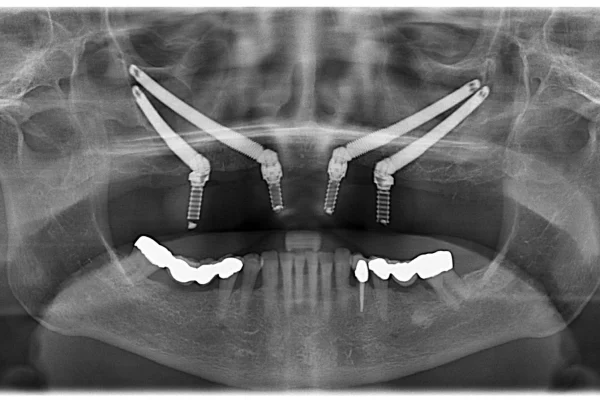

The term “All-on-4 dental implants” has become synonymous with a groundbreaking shift in restorative dentistry, offering a robust and aesthetically pleasing solution for individuals who have lost most, if not all, of their teeth, or are on the verge of doing so. At its core, the All-on-4 concept, sometimes referred to as “4 in all dental implants” or simply “all on 4 implants,” represents a paradigm shift from older, often more cumbersome methods of full arch replacement. Developed and refined by Nobel Biocare, the All-on-4® treatment concept is ingeniously designed to support an entire arch of prosthetic teeth – upper or lower – using just four strategically placed dental implants. This might sound deceptively simple, but the biomechanical principles underpinning it are sophisticated. Two implants are typically placed vertically in the anterior (front) part of the jaw, where bone density is often higher. The crucial innovation lies in the placement of the two posterior (back) implants, which are often tilted at an angle (up to 45 degrees). This angulation is key: it allows for longer implants to be used, increasing bone-to-implant contact and providing superior stability, often even in patients with reduced bone volume, thereby frequently circumventing the need for extensive bone grafting procedures – a significant advantage that shortens treatment time and reduces complexity. This technique effectively leverages the denser bone available in the jaw, making it “The original graftless full-arch solution on four implants” for many. The revolutionary aspect isn’t just the reduced number of implants but the immediacy it can offer. Patients can often leave the dental surgery with a fixed, albeit temporary, full set of teeth on the same day the implants are placed, a concept often marketed as “teeth in a day.” This immediate functionality and aesthetic improvement are truly life-altering, marking a significant departure from traditional protocols that could involve months of waiting with removable dentures or no teeth at all. The established nature of this treatment, as evidenced by its widespread adoption and even its own Wikipedia page (“All-on-4 – Wikipedia”), speaks to its efficacy and the profound impact it has had on countless individuals seeking a permanent, reliable, and natural-looking smile restoration. Its significance in modern dentistry cannot be overstated; it has democratised access to fixed full-arch solutions, offering hope and tangible results to those who previously faced limited or less desirable options. The transformative potential is immense, moving beyond mere dental repair to a comprehensive enhancement of well-being.

Embarking on the All-on-4 journey involves a meticulously planned sequence of steps, designed to ensure predictability, safety, and optimal outcomes. The “Stages of All-on-4 implant treatment” typically commence with an in-depth initial consultation. During this phase, your dental surgeon will conduct a thorough oral examination, discuss your medical history, and understand your aesthetic goals and functional needs. Advanced diagnostic imaging, often including a Cone Beam Computed Tomography (CBCT) scan, is crucial. This provides a 3D view of your jawbone, allowing for precise planning of implant placement, assessing bone density and volume, and identifying the location of vital structures like nerves and sinuses. “What does the all on four procedure involve?” at its heart is the surgical placement of four titanium implants into the jawbone. These biocompatible posts act as artificial tooth roots. As mentioned, two implants are usually placed in the front of the jaw, and two are placed at an angle in the back. This strategic angling is a hallmark of the All-on-4 technique, maximizing the use of available bone and often avoiding the need for bone grafting. “How does the All on 4 procedure work?” on the surgical day involves the administration of appropriate anaesthesia or sedation to ensure your comfort. Any remaining failing teeth in the arch are extracted, the jawbone is prepared, and the implants are precisely inserted according to the pre-operative digital plan. Often, a provisional (temporary) full-arch prosthesis is then attached to these implants on the same day or very shortly after. This allows patients to leave with a fixed set of teeth, restoring aesthetics and some degree of function almost immediately. From a patient’s perspective, “What does the All-on-4 dental implant procedure look like?” means a significant transformation often within a single day, although the overall treatment timeline spans several months to allow for healing and the creation of the final, permanent prosthesis. “Achieving the Perfect Result with All on Four Dental Implants” hinges significantly on the skill and experience of the implant surgeon and the prosthodontist, as well as the quality of the dental laboratory involved in crafting the prosthesis. Careful planning, precise execution, and meticulous attention to detail at every stage are paramount for a successful and long-lasting outcome that not only restores function but also creates a natural, beautiful smile. The collaborative effort between the clinical team and the patient, particularly regarding post-operative care and long-term maintenance, is also a critical component.